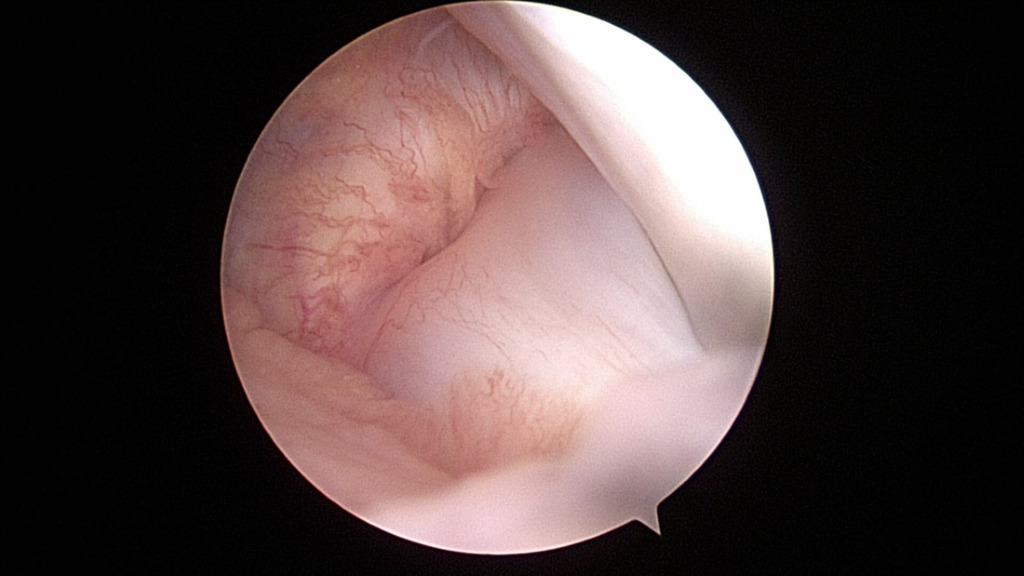

At the time of surgery, diagnostic arthroscopy revealed intact cartilage without any defects or abnormal wear. There was no evidence of a ligamentous injury. The medial meniscus was found to be intact (Figure 4).